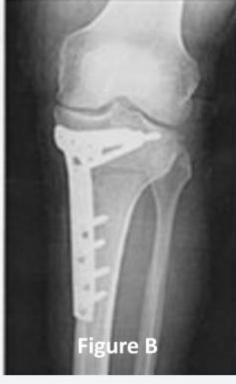

Q9: A 45-year-old male complained of left knee pain for 3 years that didnโt improve with conservative treatment. His x-ray is shown in Figure A. He underwent the procedure, as seen in Figure B. What is the aim of this procedure?

- B. Redistribute the patientโs weight.